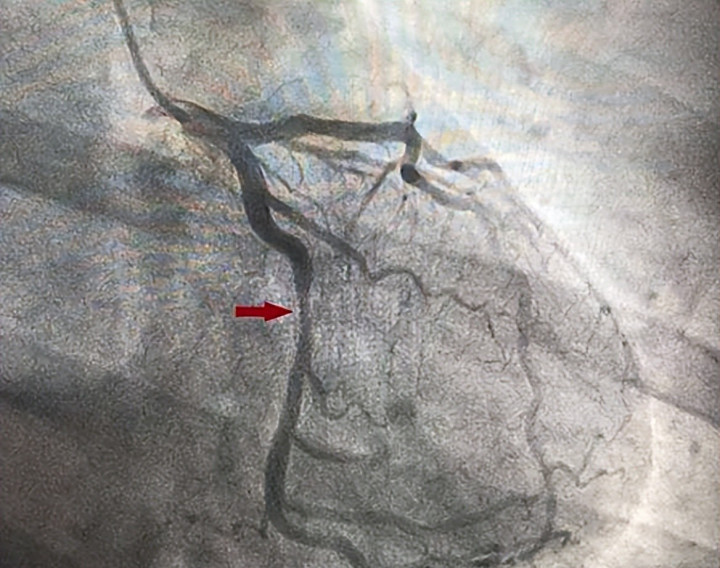

冠脉造影呢,就像是给这条公路做一次全面的“交通大检查”,能清晰地看到支架的情况和整条公路是否畅通。但这项检查毕竟是有创的,也有一定的花费和微小的风险,总不能月月查、年年查。所以,什么时候该查,什么时候可以缓缓,咱们得讲究个科学策略,既不能漏掉重要“险情”,也别花冤枉钱、让身体承受不必要的检查。

当初的“施工”难度大不大? 如果当时放置支架的血管病变特别复杂,比如是主干道分叉的地方、血管钙化很重像石头一样硬,或者一次放了好几个支架,医生可能会基于更谨慎的考虑,建议在术后半年到一年左右进行一次计划性的复查,以确保万无一失。